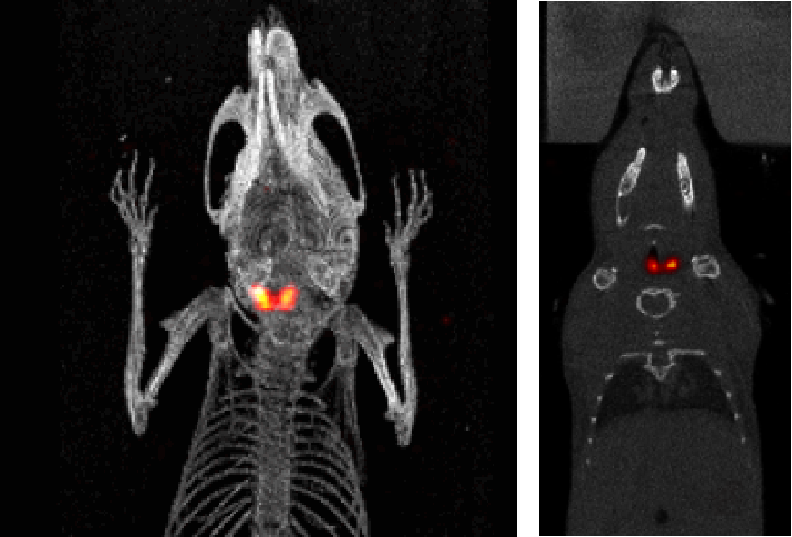

5、甲状腺SPECT成像

I123小鼠甲状腺SPECT成像:检测小鼠的甲状腺,9.4MBq(250µCi)I123,采集时间:30min。